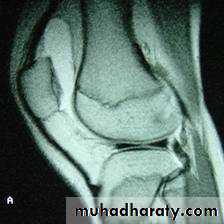

Imaging :-

Plain x-ray are normal but MRI are reliable method for diagnosis that are missed by arthroscopy .Arthroscopy :-

Investigation